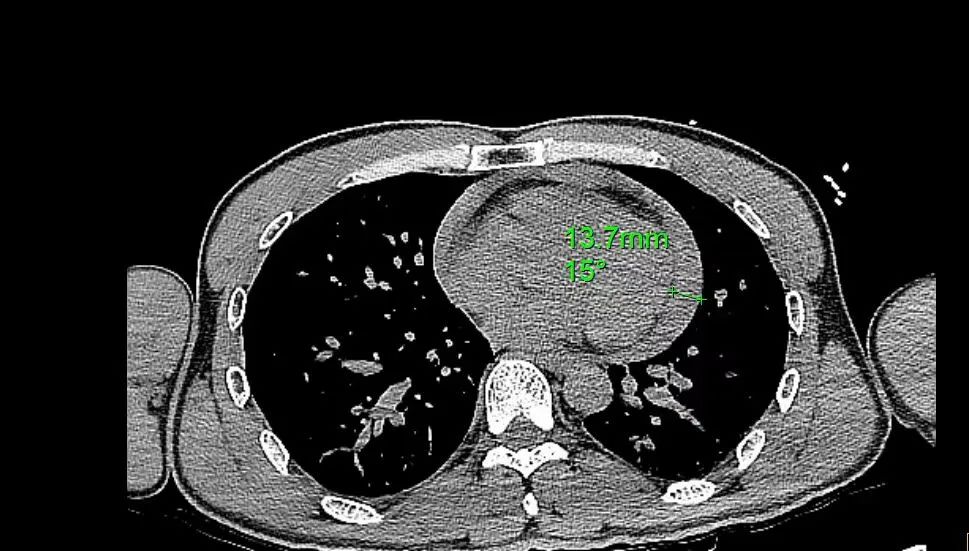

▲术前患者CT检查